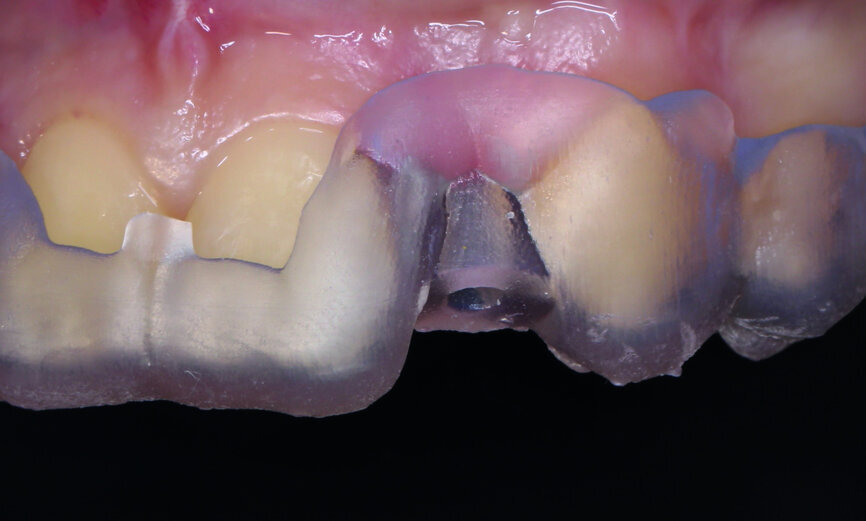

Fig. 5: Surgical guide was fabricated for maximum precision.

Fig. 6: Successful placement of the implant.

Fig. 7: Successful placement of the implant.

In this particular case, we started with an aesthetic analysis of the patient’s CBCT data and concluded that a Straumann implant with a 2.9 mm diameter would fit in the area of tooth 22, if we used a surgical guide for maximum precision (Figs. 3–5). For tooth #12, we decided to fabricate a thin-walled IPS e.max ceramic restoration (Ivoclar Vivadent).

Thanks to digital planning and a carefully fabricated surgical guide, the implant was placed successfully, even though the anatomical conditions appeared to be less than advantageous. We achieved a torque of 30 Ncm and attached a healing abutment to the implant (Figs. 6 & 7).